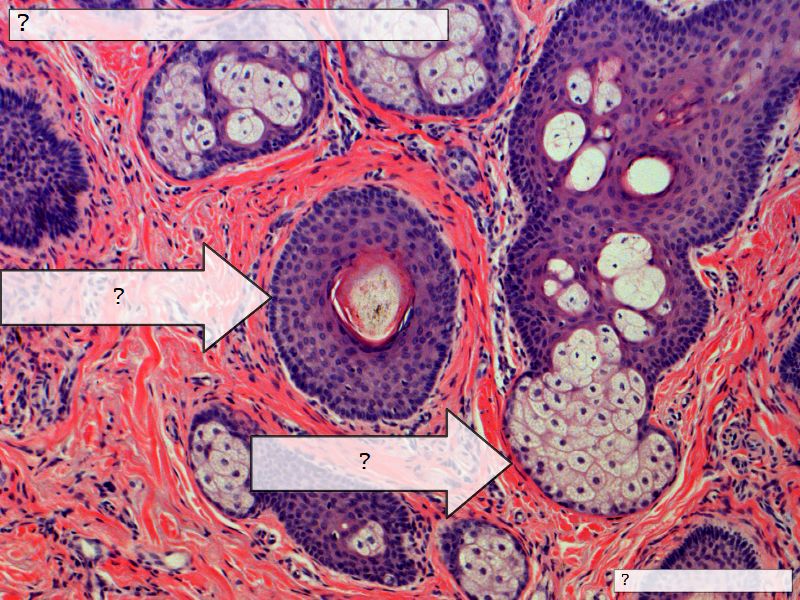

Fill in all the missing labels, and assess as you move through the slides. Answers on the down slide. It is important to do this using pen and paper, and not just glance through the images.